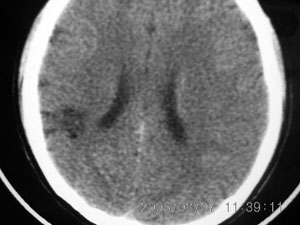

标题: CT4285:头部病变,女 21岁

女 21岁 发作性面色发白一年,每次发作仅数秒钟

脑血管畸形,建议做增强

局限性脑软化灶、脑萎缩,考虑动静脉畸形。

局部软化灶,脑沟增宽加深,考虑为脑血管畸形可能,建议增强或mri检查.

左颞顶叶不规则低迷度影边界尚清楚,岁数年轻,应考虑脑血管畸形。建议强化或核磁,进一步检查。